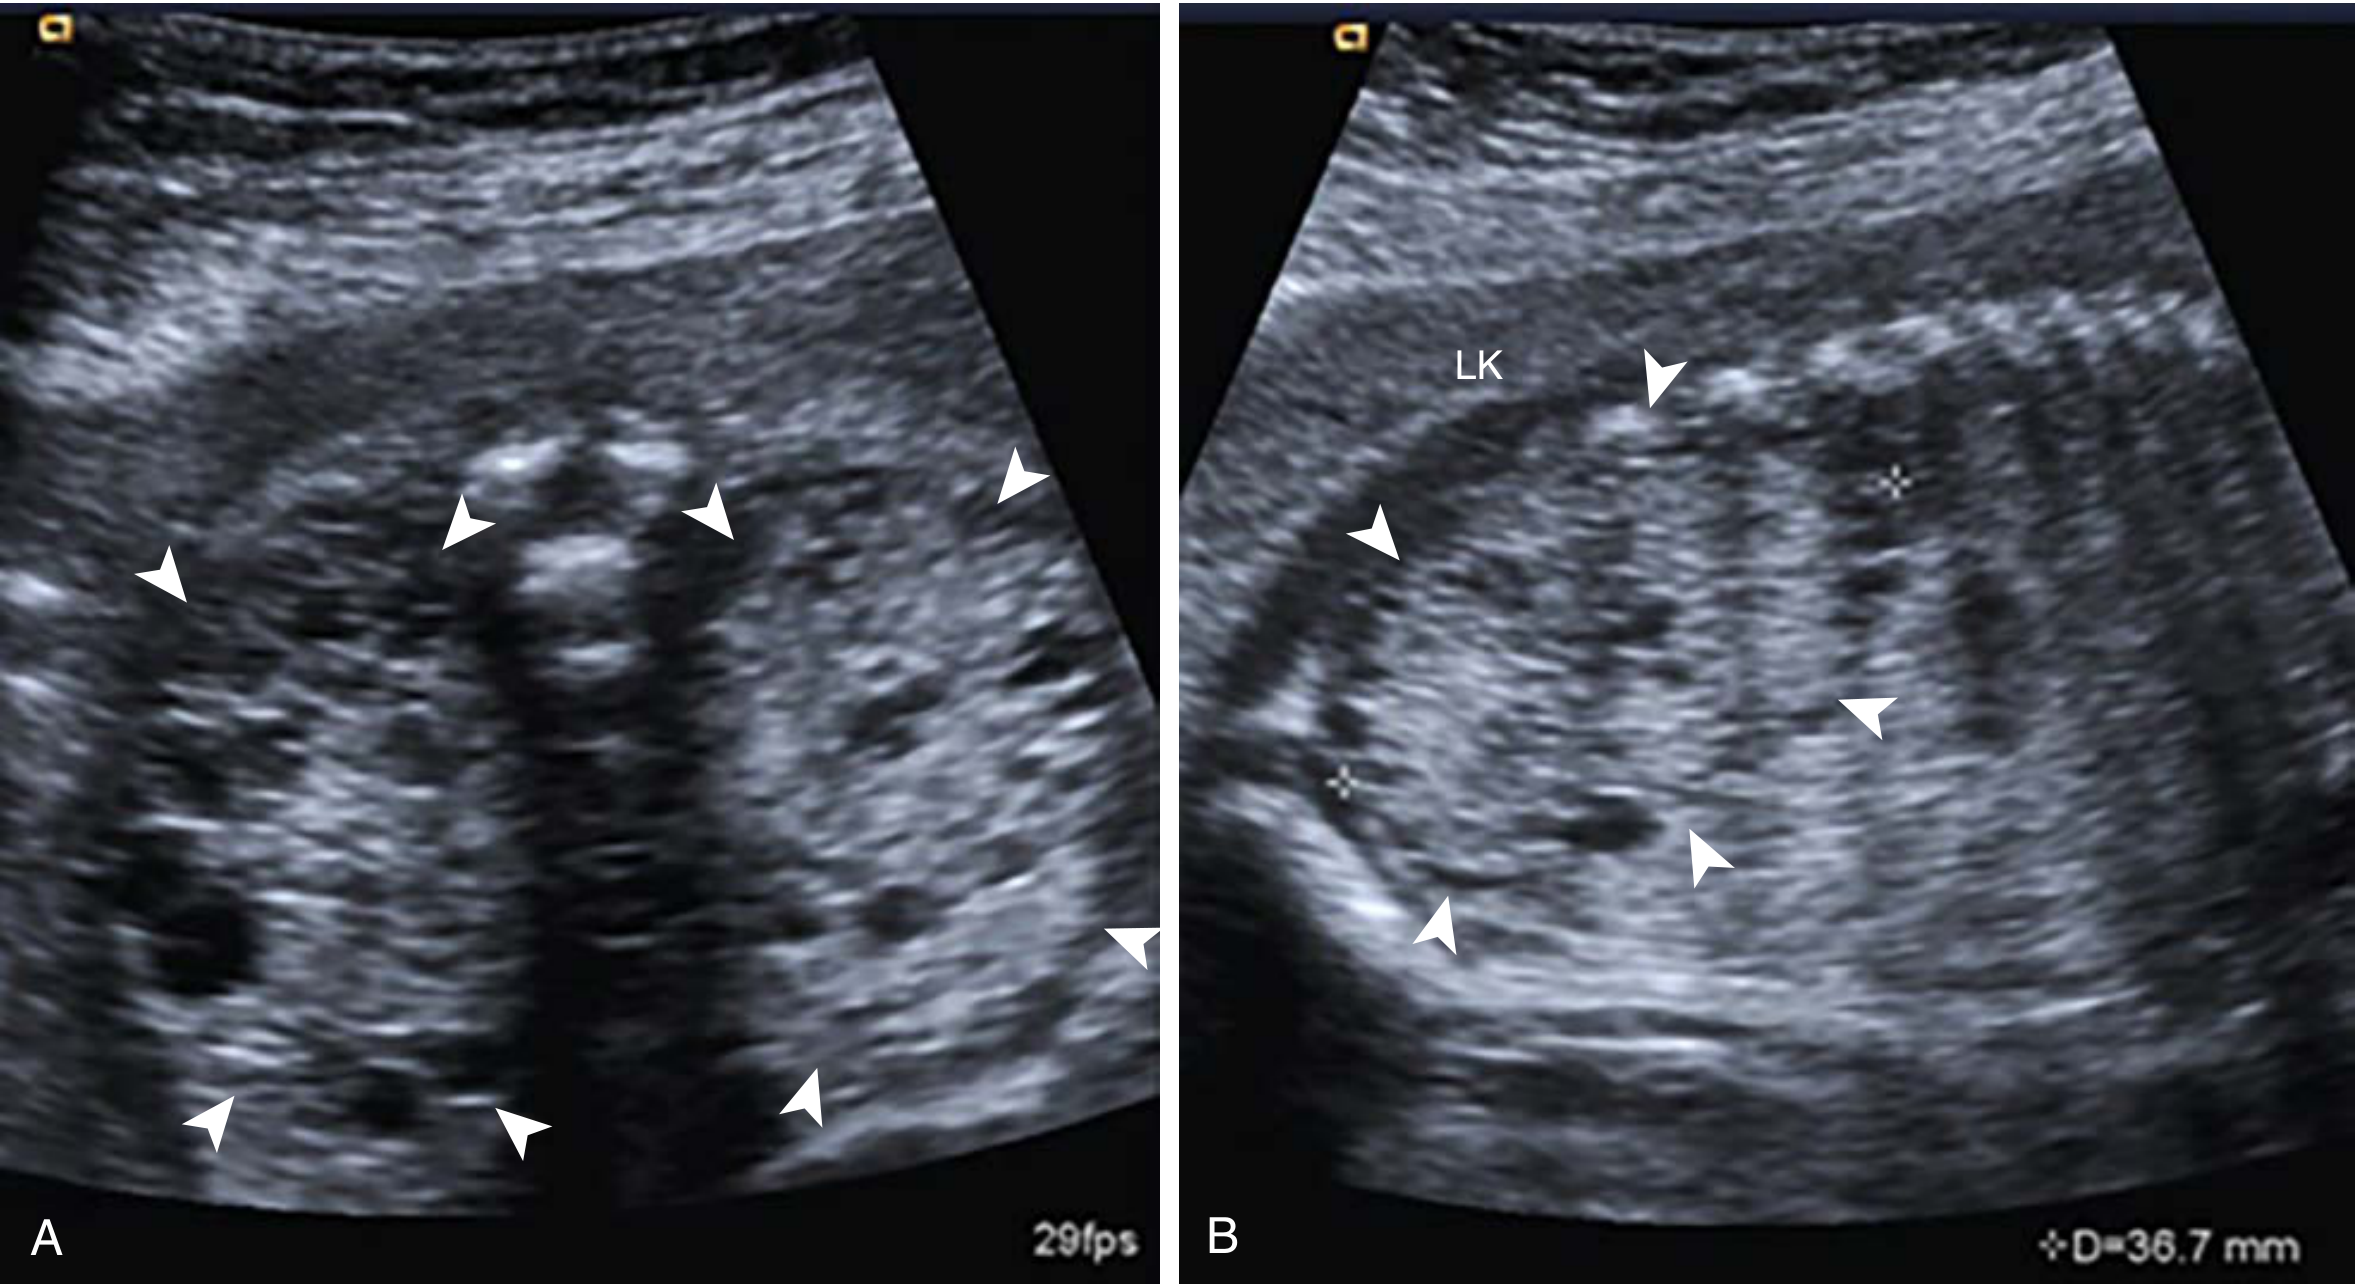

ADPKD at 31 weeks — bilateral echogenic kidneys with prominent corticomedullary differentiation, normal amniotic fluid

ADPKD at 31 weeks — echogenic kidneys with preserved corticomedullary differentiation (Creasy & Resnik's Maternal-Fetal Medicine)